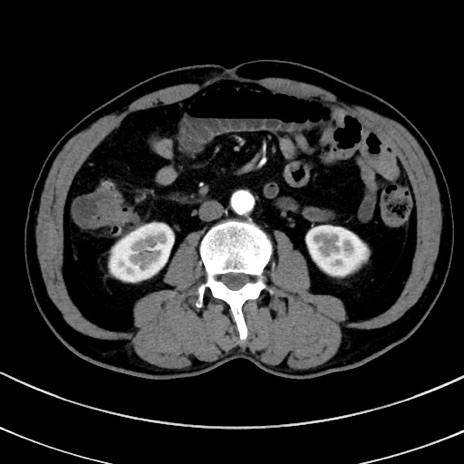

症例8(横断像)

【症例】 60歳代男性

【主訴】 黒色吐物

【現病歴】 4日前から嘔気自覚、2日前の朝食後にも嘔気あり、自分で手で嘔吐反射起こし嘔吐したところ血が混ざっていたため受診。

【既往歴】 5年前汎発性腹膜炎を伴う急性虫垂炎で手術、高血圧、前立腺肥大症、高脂血症

【身体所見】 腹部正中に手術癩痕あり 腹部平坦・軟圧痛なし膨満感あり

【データ】WBC 8400、CRP 4.54